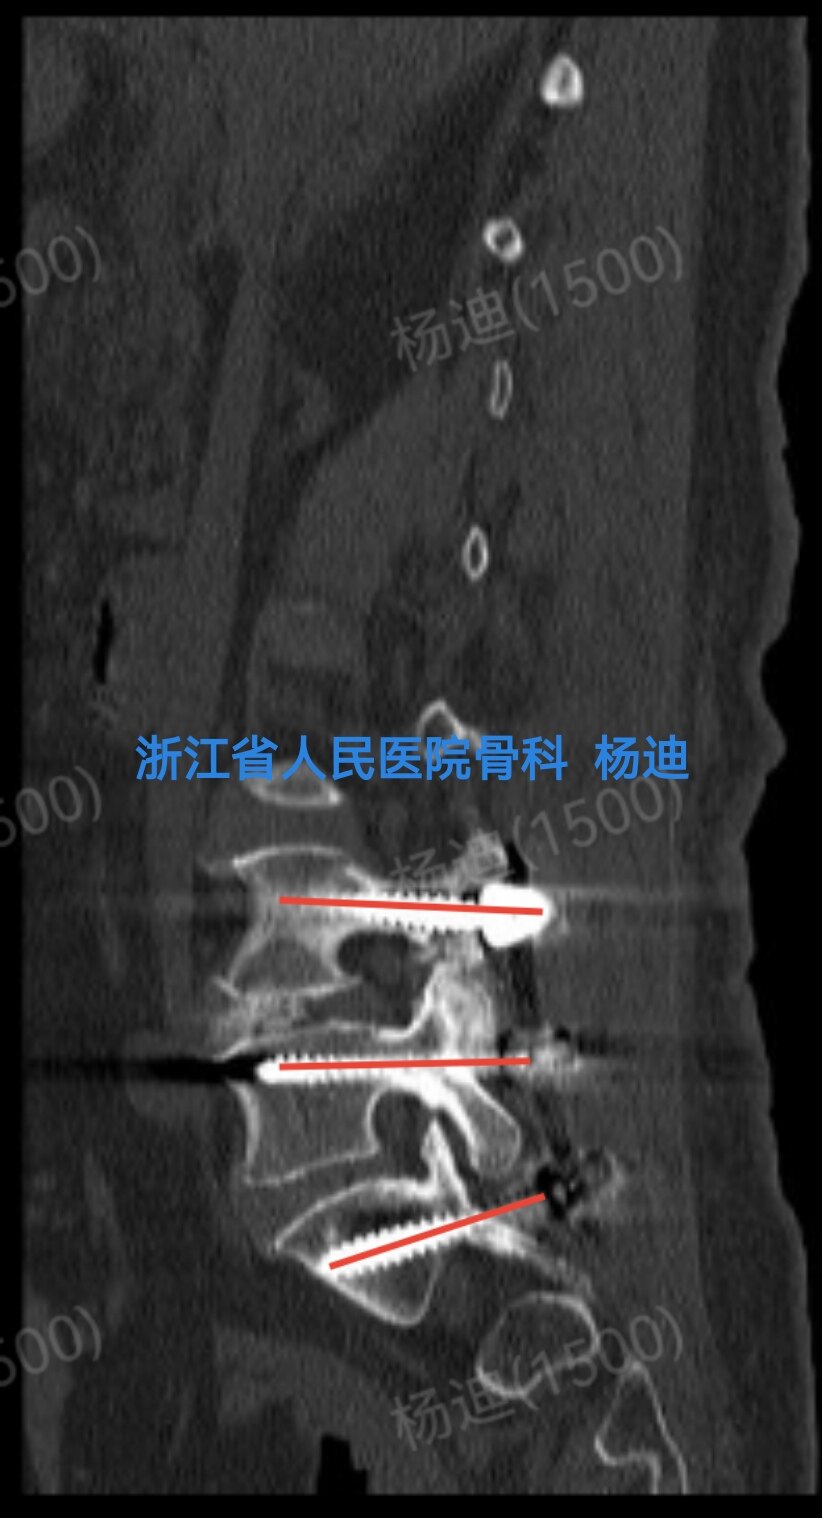

图为术后腰椎CT矢状位重建,提示左侧腰4、腰5、骶1螺钉位置及长度满意(红色直线)。

图为术后腰椎CT矢状位重建,提示右侧腰4、腰5、骶1螺钉位置及长度满意(红色直线)。